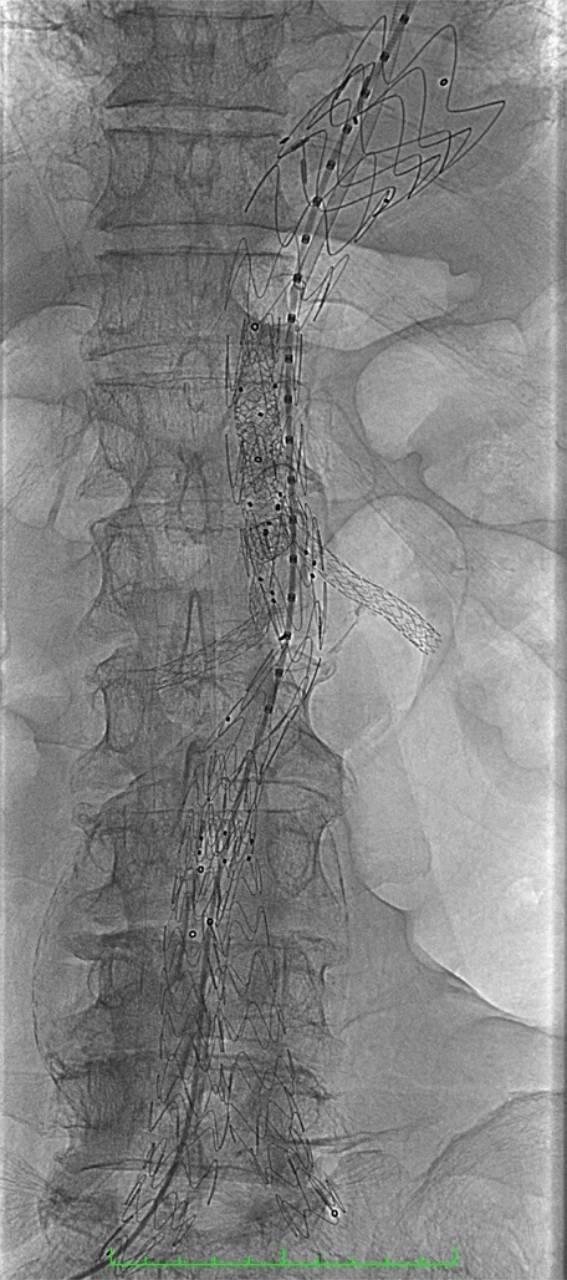

The procedure involved deployment of a custom-made E-xtra Design Multi-branch (EDM) stent graft, with meticulous cannulation and sequential stenting of the visceral arteries via the left brachial approach, including the right renal, left renal, superior mesenteric, and celiac arteries. The iliac limbs were subsequently deployed and optimized with post-dilation.

This complex intervention was performed as part of a staged repair strategy, with the second stage — Thoracic Endovascular Aortic Repair (TEVAR) completed on September 18, 2025 using the Medtronic Valiant system. The staged approach was carefully planned to reduce the risk of spinal cord ischemia during treatment of the extensive thoracoabdominal aneurysm.

Notably, the successful completion of this complex repair required the integration of endovascular technologies from two different device platforms, combining the Artivion E-xtra Design Multi-branch (EDM) stent graft for visceral branch preservation and the Medtronic Valiant thoracic stent graft system for the staged thoracic repair—demonstrating the importance of cross-platform innovation and collaboration to achieve optimal patient outcomes.